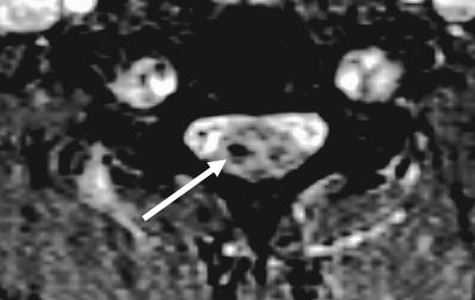

Особую категорию составляют пациенты, у которых, несмотря на наличие неврологической симптоматики, не выявляется изменений при рентгенографии или КТ. Число таких пациентов составляет около 10%. Среди различных механизмов подобных травм наиболее вероятна кратковременная компрессия спинного мозга задней продольной связкой и дисками, либо, жёлтой связкой и пластиной дуги. Посколько резкие сгибания и разгибания наблюдаются при высокой подвижности в сегментах, такие травмы более вероятны в шейном отделе позвоночника. Спондилолиз усугубляет эту ситуацию, приводя к центральному синдрому спинного мозга. В этих случаях необходимой является МРТ позвоночника. Характерными находками, которые мы часто видим при травмах при МРТ в СПб, являются отёк спинного мозга и гематома, причём последняя при МРТ позвоночника плохим прогностическим фактором в отношении восстановления неврологического дефицита. К наиболее тяжелым осложнениям шейной травмы относится расслоение магистральных артерий, определяемое по МРТ, МРА или КТ и КТА. В высоком поле такой вид травм лучше виден чем в открытом МРТ. МРТ СПб позволяет выбирать место МРТ, однако, острая травма шейного отдела позвоночника требует высокоспециализированного нейрохирургического отделения

МРТ шейного отдела позвоночника. Острая травма. Компрессия спинного мозга, отек и контузия. Сагиттальная Т2-взвешенная МРТ.

МРТ шейного отдела позвоночника. Аксиальная Т2-взвешенная МРТ. Кровоизлияние в спинной мозг.